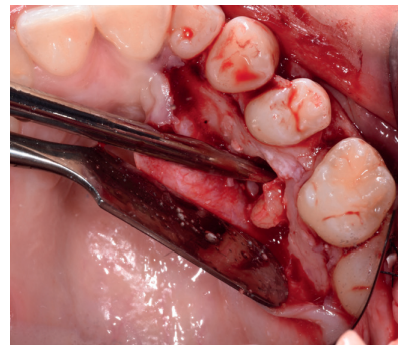

Tras el consentimiento informado, se realizó un bloqueo anestésico mediante Articaína al 4% con adrenalina 1: 100.000 del nervio dentario inferior y lingual, y posteriormente del nervio bucal. Se realizó una incisión festoneada lineal desde la cara distal del primer molar inferior izquierdo, hasta la cara distal del segundo molar inferior izquierdo, y se realizó una incisión oblicua hacia la rama ascendente mandibular. Tras el despegamiento mucoperióstico, se realizó una protección del nervio lingual durante las maniobras de ostectomía (Figura 5). Posteriormente, se realizó la ostectomía necesaria para liberar el límite amelocementario (LAC) del tercer molar inferior (Figura 6), procediendo a su luxación mediante botador recto, odontosección coronal con pieza de mano y fresa redonda de carburo de tungsteno (Figura 7), y exodoncia del fragmento radicular una vez retirado el fragmento coronal. El alveolo se lavó con suero fisiológico y se suturó la herida con seda de 4/0 (Figura 8).

Una vez suturada la herida, se procedió a la extracción del premolar retenido en posición 2.5, para lo cual, tras el bloqueo anestésico de los nervios alveolares superiores posterior, medio y anterior y del nasopalatino y palatino mayor, se realizó una incisión festoneada lineal en la mucosa palatina, y un despegamiento mucoperióstico desde distal del primer molar superior izquierdo hasta distal del incisivo lateral superior izquierdo (Figura 9). Tras el despegamiento, se realizaron las maniobras de ostectomía con pieza de mano y fresa de carburo de tungsteno, la odontosección coronal, y la exodoncia del fragmento coronal y radicular (Figura 10). Al observar la cavidad resultante (Figura 11), se apreció una perforación en la membrana del seno maxilar (Figura 12), en la que se colocó una membrana reabsorbible de colágeno (XFina, Osteógenos®, Madrid, España), de manera previa a la colocación del injerto de dentina (Figura 13). Se le hizo morder al paciente una gasa estéril empapada en clorhexidina al 0,12%, durante la preparación del material de injerto.